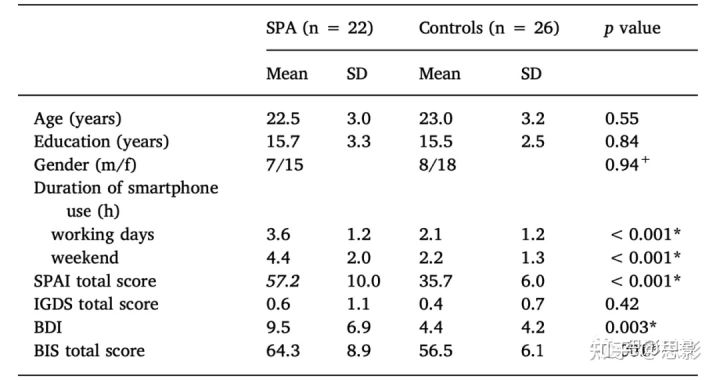

表1:智能手机成瘾者(SPA)和对照组的人口统计学和临床分数。

数据以平均值和标准差(SD)的形式给出。SPAI:智能手机成瘾量表; IGDS:网络游戏障碍量表; BDI: Beck抑郁量表; BIS: Barratt冲动性量表11版。+表示χ2检验; *表示(t检验)有显著性结果,p < 0.05。

SPA患者和对照组在年龄、性别和教育年限方面没有显著差异。正如预期的那样,SPA患者花在智能手机上的时间明显更多,就SPAI总分而言,组间存在显著差异。各组间BDI(Beck抑郁量表)、BIS(Barratt冲动性量表)总分差异有统计学意义(详见表1)。参与者具体的智能手机使用活动如表2所示。